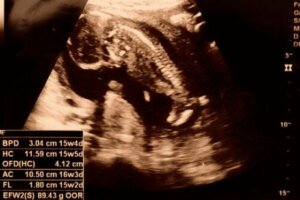

초음파 사진을 통해 처음으로 태아의 성별을 가늠할 수 있는 시기가 바로 임신 15주 차이다. 그뿐 아니라 태아의 팔, 다리가 성장하고 관절을 풀 수 있다.